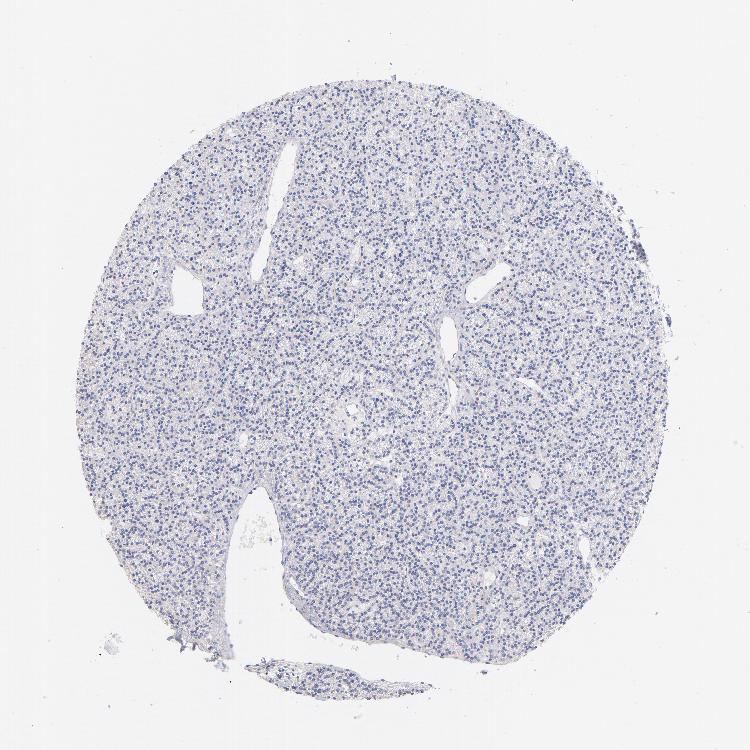

PARATHYROID GLAND - Antibody stainingi

Antibody staining in the annotated cell types in the current human tissue is reported as not detected, low, medium, or high, based on conventional immunohistochemistry profiling in selected tissues. This score is based on the combination of the staining intensity and fraction of stained cells.

Each image is clickable and will lead to virtual microscopy that enables deeper exploration of all samples and also displays staining intensity scores, fraction scores and subcellular localization as well as patient and tissue information for each sample.

Antibody HPA002042

Glandular cells Not detected